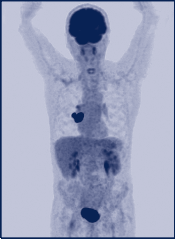

Skelettszintigramm bei einem Patienten mit ossär metastasiertem Prostatakarzinom. Dabei zeigen sich Metastasen im Brustbein, in der Wirbelsäule sowie im Beckenskelett und den Extremitäten.

Zur Skelettszintigraphie werden Tc-99m-markierte Phosphonate verwendet. Die spezifische Anreicherung im Knochen erfolgt durch Adsorption, die Speicherung wird durch die Osteoblastenaktivität bestimmt. Szintigraphisch stellt sich der Randsaum der durch Zytokine aktivierten Mineralisationssteigerung dar, welcher größer als die Tumorzellmasse ist. Dies bedeutet, dass Metastasen szintigraphisch deutlich früher als röntgenologisch zu detektieren sind. Der Metabolismus ist in osteoblastischen Metastasen etwa 20-fach, bei osteolytischen Metastasen etwa 3-fach höher. Daher sind osteoblastische Metastasen besonders sensitiv in der Szintigraphie nachzuweisen, dagegen weisen osteolytische Metastasen in der FDG-PET eine hohe Detektionsrate auf. Beim Prostatakarzinom dominieren osteoblastische Metastasen, daher ist die Skelettszintigraphie hier besonders sensitiv. Beim Mammakarzinom, Pankreaskarzinom und Magenkarzinom sind osteoblastische und -lytische Metastasen etwa gleich häufig, bei allen anderen Tumoren existieren überwiegend osteolytische Metastasen. Beim Prostatakarzinom ist die Wahrscheinlichkeit einer Skelettmetastasierung vom PSA-Wert abhängig. Bei einem PSA <1 ng/ml liegt die Wahrscheinlichkeit unter 1%, bei PSA-Werten von >100 ng/ml über 50%. Die Skelettszintigraphie wird von der Deutschen Gesellschaft (DG) für Urologie ab einem PSA-Wert von über 10 ng/ml empfohlen, die DG für Radioonkologie empfiehlt die Szintigraphie vor der Strahlentherapie des Mammakarzinoms. Beim nichtkleinzelligen Bronchialkarzinom soll die Skelettszintigraphie präoperativ erfolgen (DG für Thoraxchirurgie). Bei ossären Malignomen erfolgt die Skelettszintigraphie in Dreiphasentechnik, um neben dem Osteometabolismus auch Perfusion und Blood-Pool darzustellen, die unter Therapie entscheidende Hinweise auf Prognose und Therapieansprechen liefern können. Weiterhin lassen sich szintigraphisch hochsensitiv Fernmetastasen nachweisen.